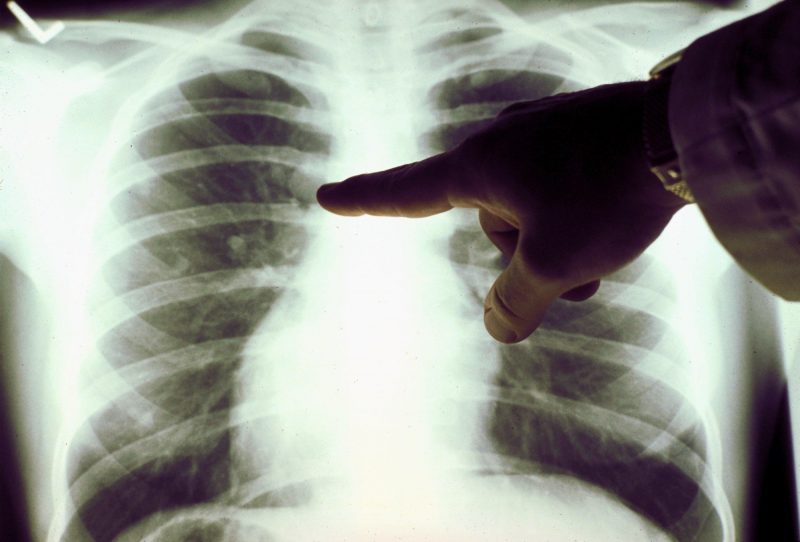

Успешность постановки диагноза на представленном этапе напрямую ассоциируется с корректным применением рентгеновского оборудования. Также очень важно правильно предположить локализацию новообразования (на основе существующих симптомов). Следует учитывать, что именно ранняя идентификация патологии способна сохранить человеческую жизнь. На счет видимости рака легких на рентгене, следует обратить внимание на следующие нюансы:

- на рентгеновском снимке не будет виден такой узел, который располагается внутрибронхиально. Единственным признаком, формирующим представление о патологии, следует считать гиповентиляцию одного из легочных сегментов;

- средостенное расположение узлового формирования выглядит как неоднородное затемнение. Ему характерна средняя степень интенсивности и сливание с грудной клеткой;

- такой форме рака свойственны определенные характеристики: примыкание диаметра тени обширной частью к грудине, наличие острого угла между грудной клеткой и затемненной частью;

- на начальном этапе рака легочной системы на боковой проекции грудины присутствует тень, по форме напоминающая шар.

При раке легких, рентген далеко не всегда в состоянии со 100% достоверностью определить патологию. Именно поэтому специалисты настаивают на ряде дополнительных обследований, которые вместе с описываемым методом, сформируют полноценную картину. Говоря об этом, обращают внимание на КТ, МРТ и радиосцинтиграфию.